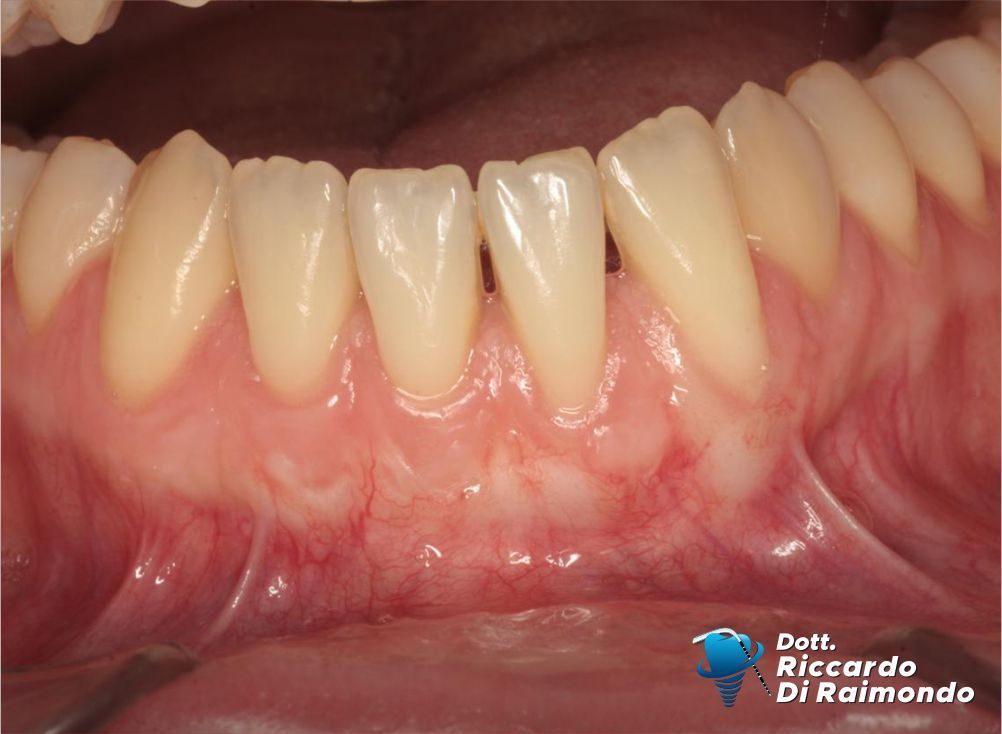

Considerate queste condizioni, ho pianificato un intervento di chirurgia plastica parodontale (chirurgia mucogengivale) con l’obiettivo di ottenere la copertura radicolare e, allo stesso tempo, migliorare la qualità e lo spessore dei tessuti gengivali, aumentando la stabilità biologica nel lungo periodo.

Questo approccio consente non solo di ottenere un miglioramento estetico significativo, ma soprattutto di modificare il fenotipo gengivale, creando condizioni biologiche più favorevoli alla stabilità dei tessuti nel tempo.

Fine Trattamento